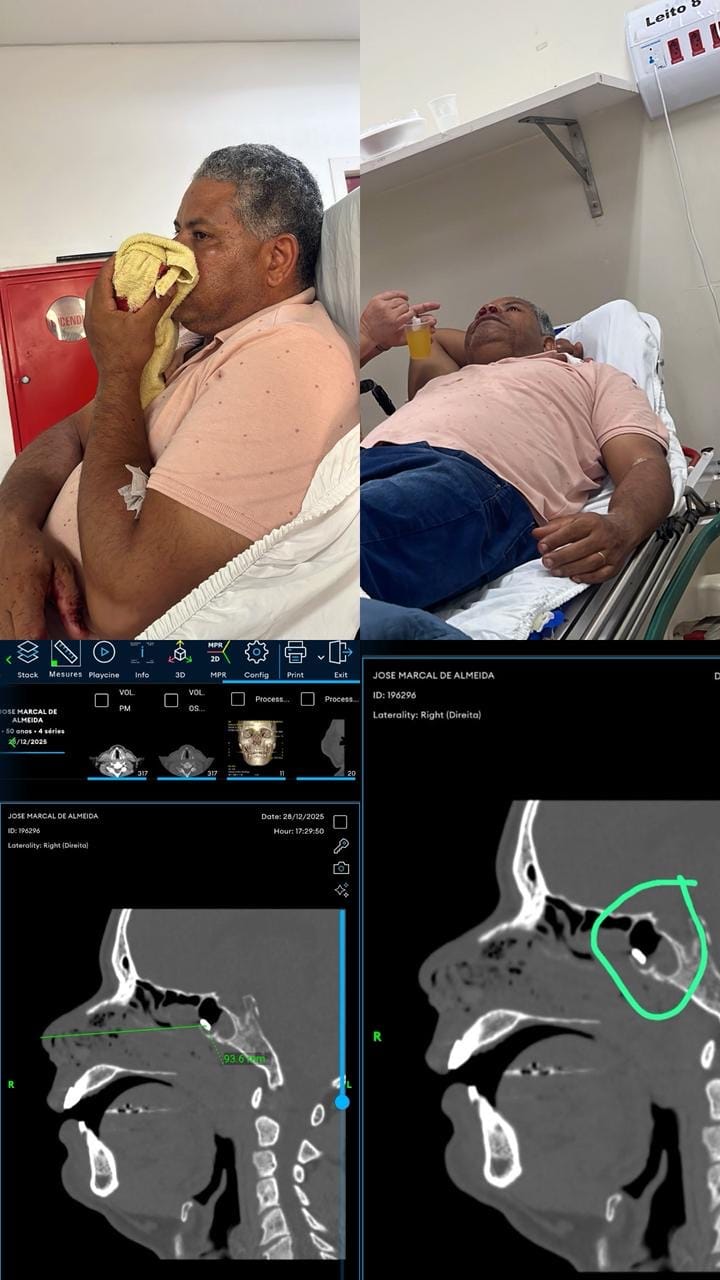

Uma família de Cuiabá denuncia falhas graves no atendimento prestado pelo Sistema Único de Saúde (SUS) após um homem sofrer um acidente grave com uma roçadeira, que lançou um fragmento metálico para dentro do nariz e dos seios da face, provocando ferimento profundo e intensa perda de sangue.

Somente no domingo à noite, por volta das 18h, o paciente foi levado ao Hospital São Benedito, onde conseguiu realizar a tomografia. O exame confirmou a presença de corpo estranho alojado na face, reforçando a gravidade do caso e a necessidade de acompanhamento especializado, possivelmente cirúrgico.

Após permanecer internado entre os dias 27 e 29 de dezembro, o paciente recebeu alta hospitalar no dia 29, mesmo com o corpo estranho ainda alojado e sob risco de complicações. De acordo com os familiares, ele deixou o HMC sem receber laudo médico, relatório de atendimento, encaminhamento ou qualquer documento que garantisse a continuidade do tratamento.

Diante da situação, a família foi obrigada a buscar atendimento na rede particular, onde um médico otorrinolaringologista confirmou a necessidade de avaliação especializada e a possibilidade de intervenção cirúrgica.